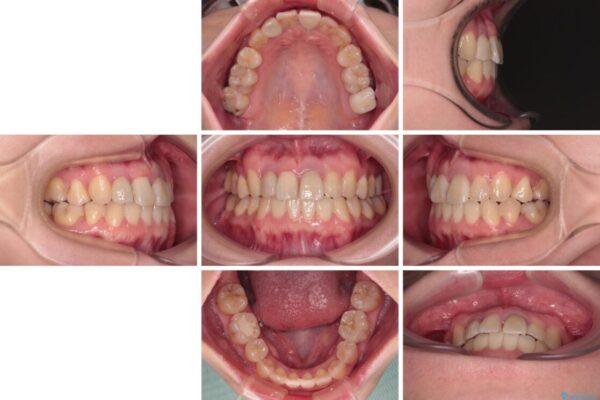

治療途中

• 虫歯治療ついでに歯並びの後戻りを改善 インビザラインによる矯正治療 治療途中画像